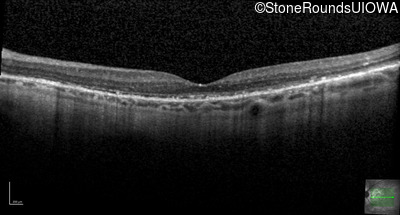

Optical Coherence Tomography - Right - 20/20 -1

Exemplar / OCT Stack

OCT Stack